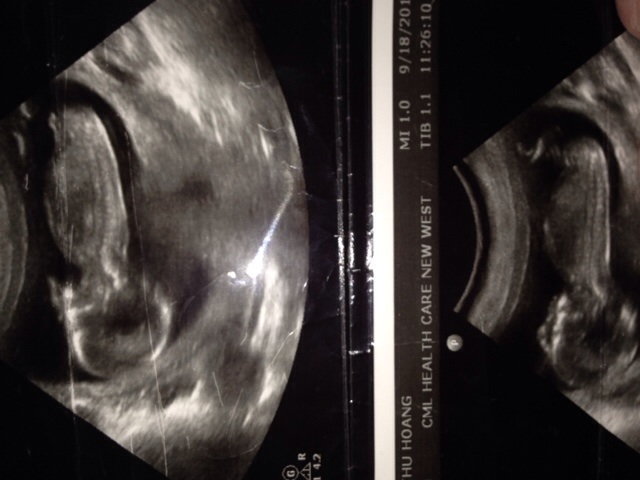

Any help for guessing my baby gender boy/girl????

PLEaSe help me guess boy or girl??? 13 weeks 5 days nub

I don't think I see a nub. Sorry!

I don't see a nub, sorry. Hope you get your girl.

not sure, sorry! Hope you get your girl